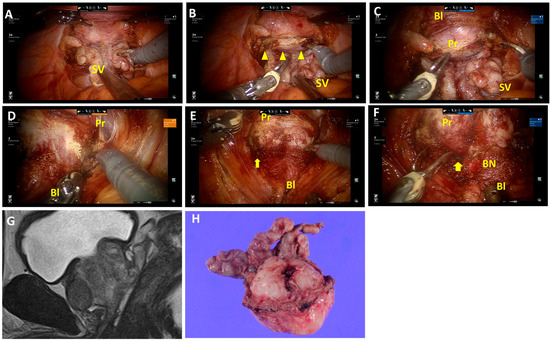

Fat tissues and vessels overlap the retrotrigonal layer (Figure 1A; Video S1) and are abundant on the lateral sides. Fat tissues and vessels, followed by the retrotrigonal layer, are transected approximately 0.5–1.0 cm above the seminal vesicle and deferens vasa. This allows the bladder wall to be separated anteriorly from the prostate (Figure 1B,C). In cases with an enlarged prostate or prominent median lobes, the retrotrigonal layer tends to be thinner, and the surface of the prostatic pseudocapsule can easily be identified after transection (Figure 2A,B; Video S2). Then, this layer can be developed anteriorly (Figure 2C). For nerve-sparing procedures, the lateral transection of the retrotrigonal layer and/or overlapping fat tissues and vessels are preserved.

The detrusor apron at the bladder neck is dissected and developed laterally (Figure 1D and Figure 2D). Then, the posterior space is opened laterally prior to the bladder neck opening (Figure 1D). Carefully, detrusor muscles are detached from the prostate, revealing the longitudinal urethral muscles in the center (Figure 1E). Then, the anterior urethral muscles are dissected to open the bladder neck, followed by the posterior bladder neck. The bladder neck is preserved (Figure 1F and Figure 2F). This procedure was consistently applied, except in cases where the prostate tumor was located near the proximal edge, adjacent to the bladder neck.

Figure 1. Surgical techniques of the retrotrigonal layer dissection from the posterior approach and bladder neck preservation. (A) Isolation of the seminal vesicle and dissection of deferens vasa in the posterior approach. (B) The retrotrigonal layer, pinkish longitudinal tissue, is transected (triangles). (C) The view after transection of the retrotrigonal layer. The bladder is separated anteriorly from the prostate. (D,E) Left lateral approach in bladder neck dissection. The posterior space is opened prior to the bladder neck opening (arrows). Detrusor muscles are detached from the prostate. (F) The bladder neck is preserved. (G,H) Magnetic resonance imaging (MRI) sagittal view and macroscopic findings of the prostate and seminal vesicle. SV, seminal vesicles; Bl, bladder; Pr, prostate; BN, bladder neck.